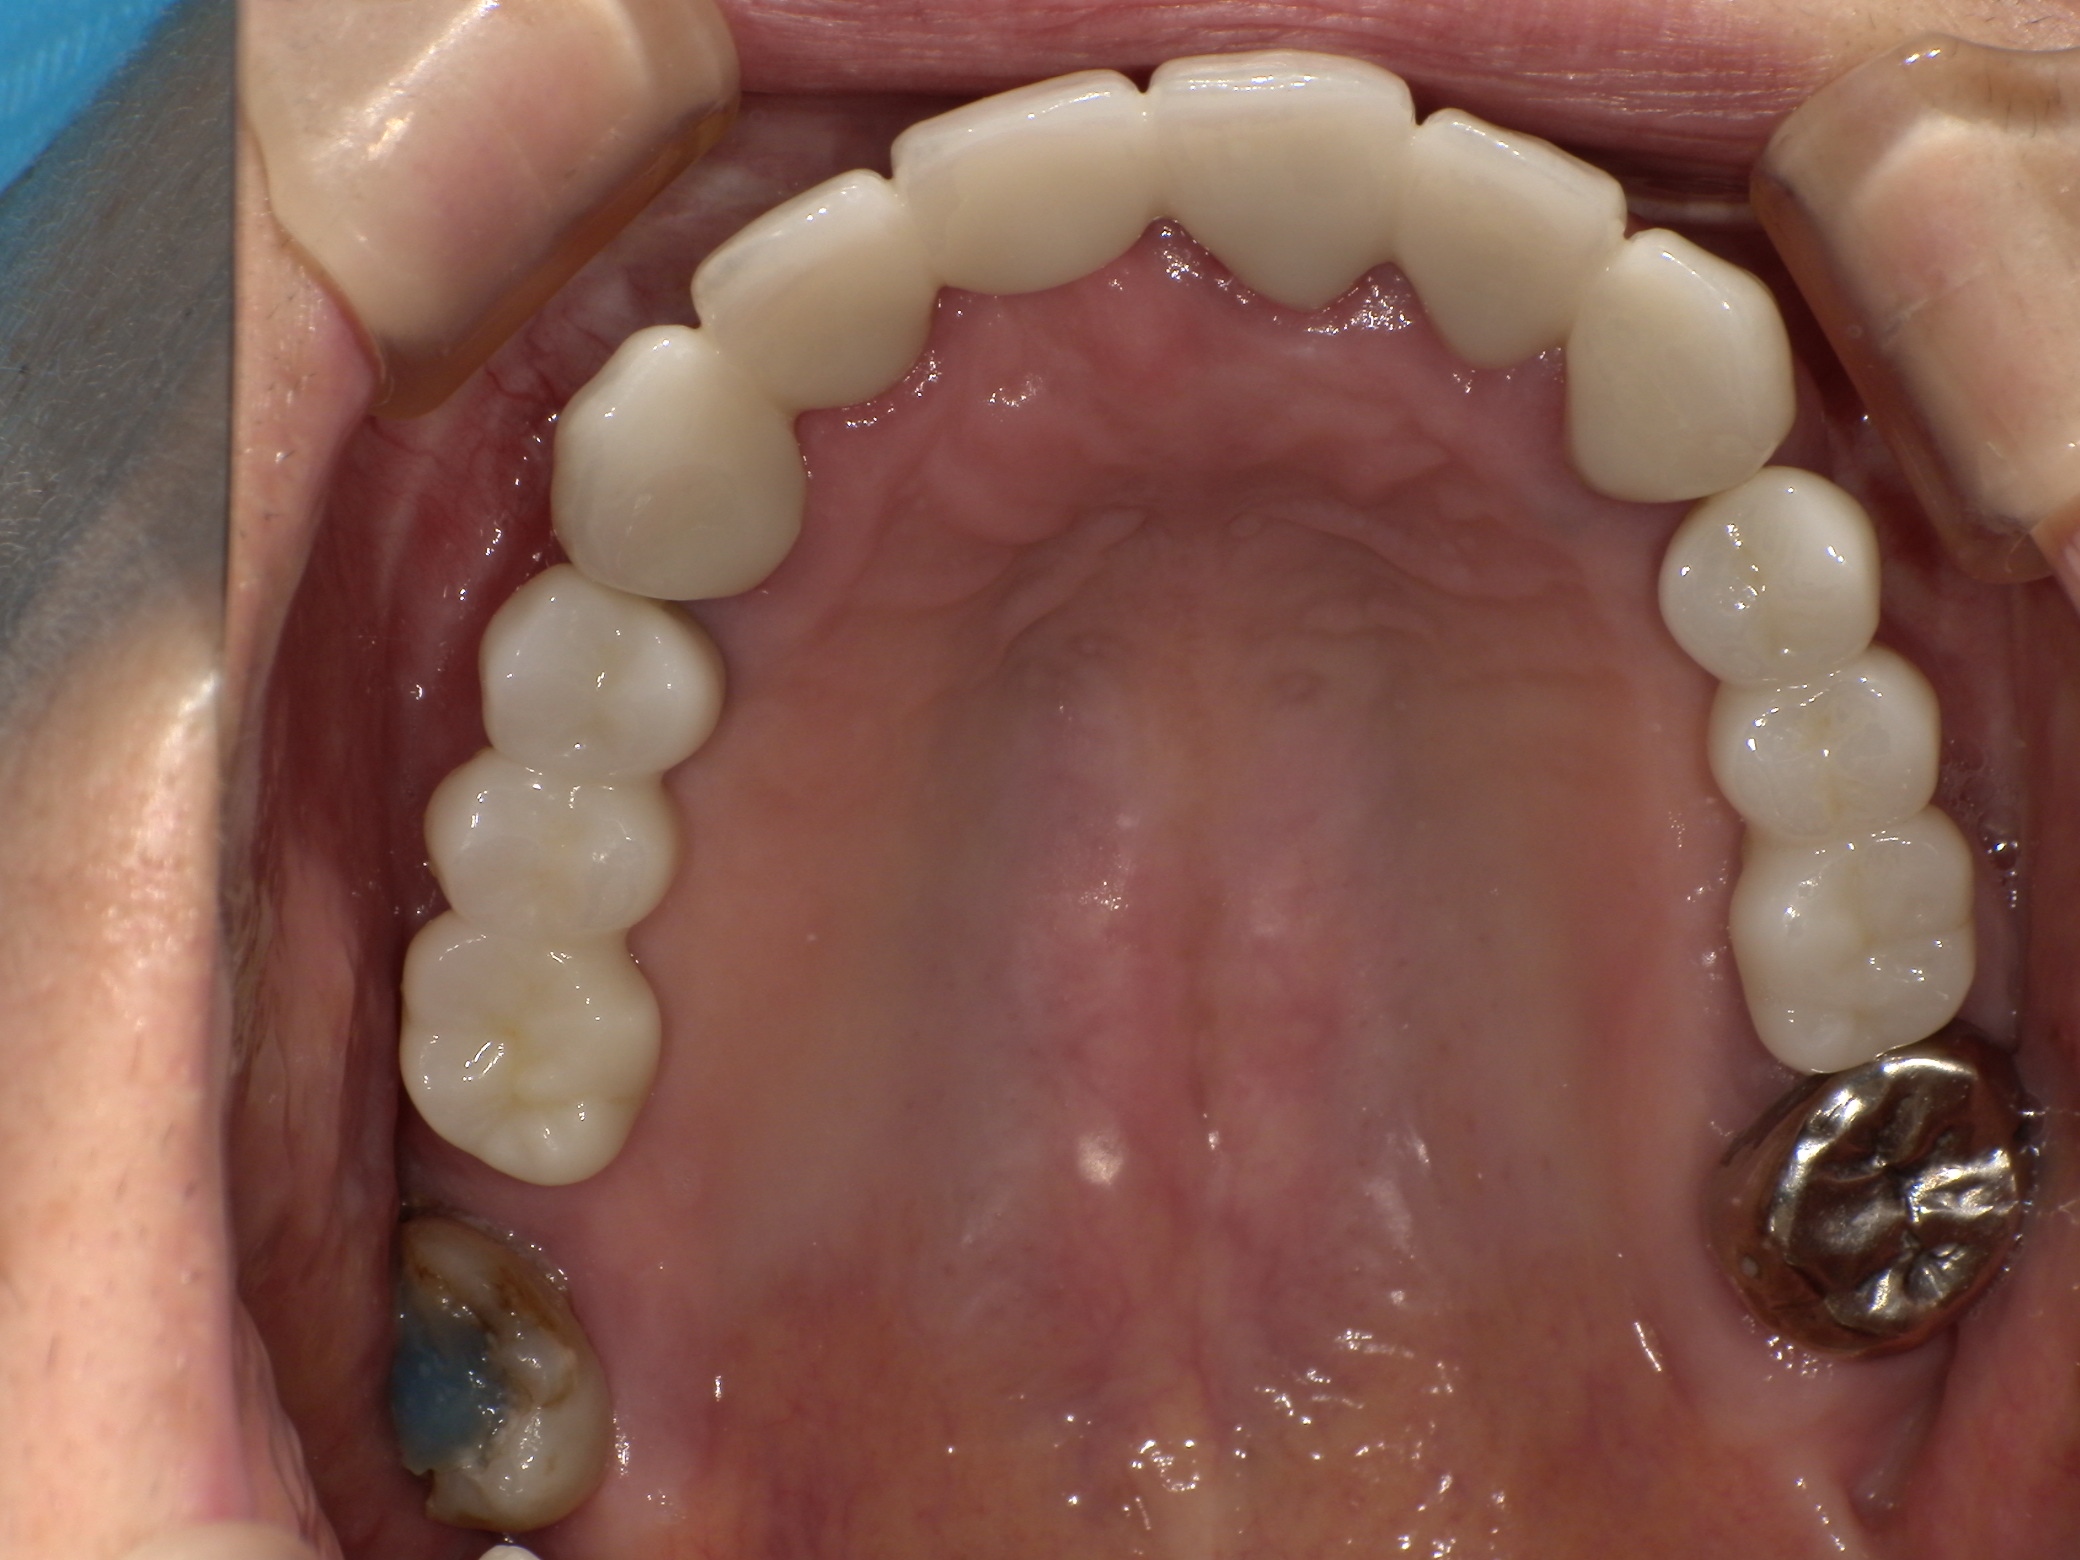

BEFORE

AFTER

主訴

全体的に見た目を綺麗にしたい。奥歯でしっかり噛みたい。

診断名・主な症状

臼歯部欠損

年齢

70歳

治療内容

インプラント埋入(右上4・6,左上4・6,右下6,左下6)

ジルコニアBr(右上3―左上3)

ジルコニア(右下5,左下5)

治療期間/

通院回数

インプラント 1年5ヶ月/13回

ジルコニアBr、ジルコニアクラウン 3ヶ月/10回

費用

インプラント: 2,552,000円

その他治療: 640,000円

合計 3,192,000円

*いずれも税込